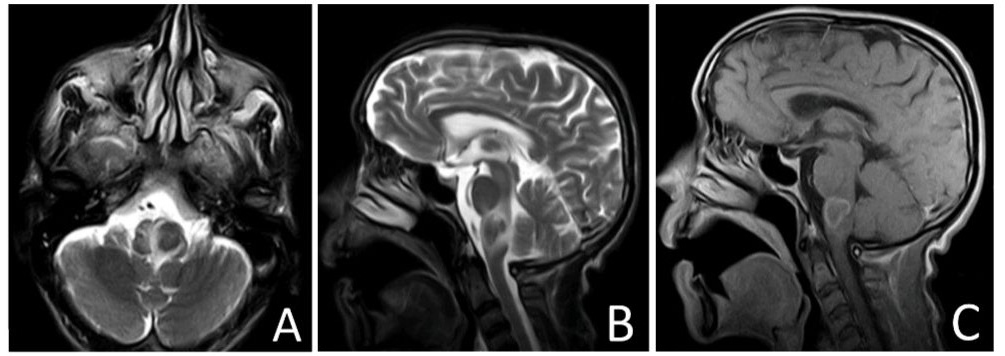

A postcontrast magnetic resonance imaging (MRI) revealed a well-defined T2 hypointense lesion in the right lateral medulla with minimal surrounding edema. The lesion showed peripheral enhancement on post contrast imaging, indicating a tuberculoma causing lateral medullary syndrome. The patient was started on anti-TB medication (Fig. 1).

Fig. 1. Axial T2 (A), Sagittal T2 (B) and Sagittal (T1 post contrast) images of the brain showing a well-defined T2 hypo intense peripherally enhancing lesion in the left lateral medulla with surrounding edema seen.